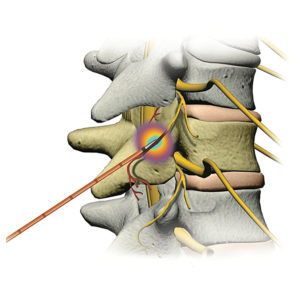

Mit der computertomographisch gesteuerten Injektionstechnik ist es möglich, die Nadel millimetergenau am gewünschten Applikationsort des Medikaments zu positionieren, wobei verschlissene und gereizte kleine Wirbelgelenke oder aber eingeengte Nervenaustrittslöcher (Neuroforamina) behandelt werden. Üblicherweise therapieren wir die erkrankten Strukturen selektiv, bedarfsweise auch aufeinander folgend, sodass später je nach erzielter Wirkung die eine oder andere Region als Hauptverursacher der Schmerzsymptomatik erkannt werden kann.

- Periradikuläre Injektion an der Lendenwirbelsäule

Periradikuläre Injektion Lendenwirbelsäule (Spritze an die Nervenwurzel unter CT-Kontrolle)